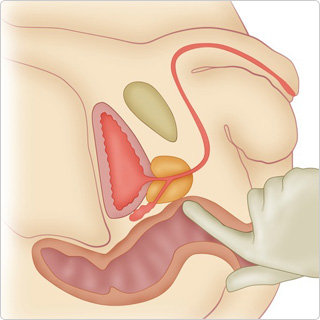

前列腺是男性独有的生殖器官,位于膀胱下方和直肠前方。它覆盖尿道,即尿液通道,并产生约 30% 的精液。如果前列腺肿大,就会压迫尿道,导致多种泌尿系统疾病。

前列腺是男性独有的生殖器官,位于膀胱下方和直肠前方。它覆盖尿道,即尿液通道,并产生约 30% 的精液。如果前列腺肿大,就会压迫尿道,导致多种泌尿系统疾病。